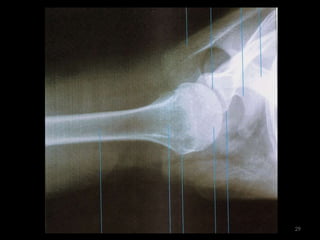

úmero51

Incidência AP Úmero52

53

54

Incidência lateral do úmero55